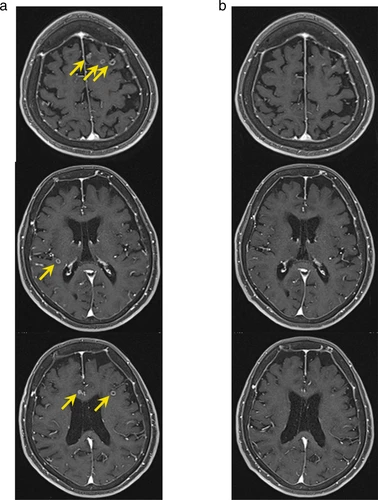

进展性卒中,又称为脑卒中后神经功能恶化,是指在脑卒中发作后,患者的神经功能逐渐恶化的情况。它不同于一次性的脑卒中,而是在短时间内出现多次脑卒中发作,导致脑组织受损加重,并且患者的神经功能逐渐减退。